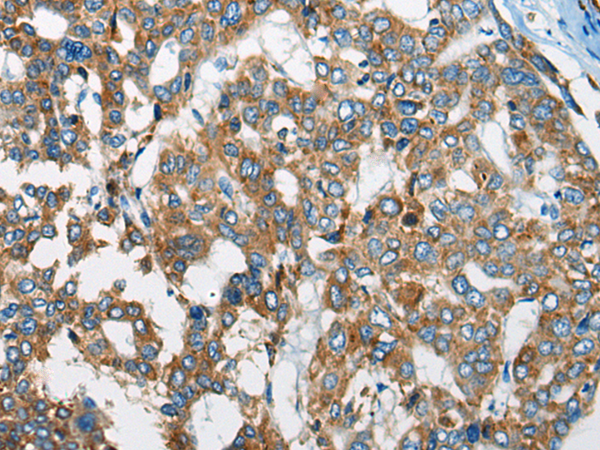

IHC positive control: |

Human liver cancer and human prostate cancer |